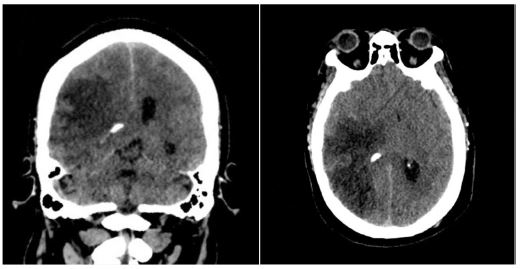

Twenty-four hours post-admission, his neurological status worsened (GCS decreased by 4 points), and a CT scan showed a significant midline shift. A right-sided frontotemporoparietal decompressive craniectomy was performed. Postoperatively, his GCS improved to 14 and motor strength improved to 3/5 on the Lovett scale (Figure 2). A Computed Tomography Angiography (CTA) performed 48 hours after surgery showed restored flow in the M1 and distal branches of the right MCA (Figure 3). A confirmatory cerebral angiogram at two weeks demonstrated patent flow throughout the MCA distribution (Figure 4).

Figure 2: Post-decompressive craniectomy computed tomography. Evidence of persistent ischemia is observed in the right MCA territory.